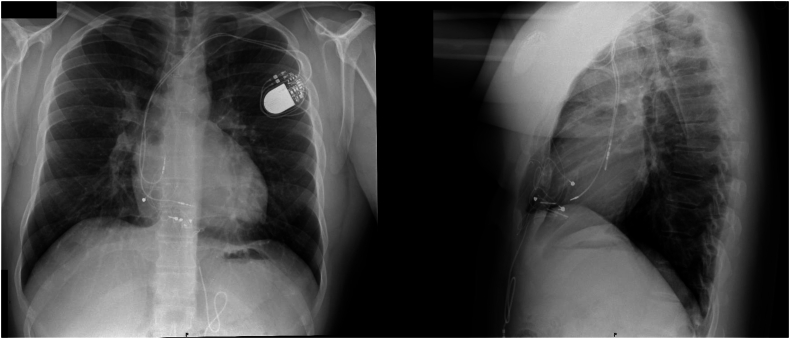

A 26-year-old male patient with a history of transposition of the great arteries status post arterial switch and VSD repair neonatally had complicated second degree atrioventricular block and sinus node dysfunction necessitating pacemaker placement. Epicardial single-chamber ventricular pacemaker was placed neonatally, which was switched to dual-chamber pacemaker at age 17 due to malfunction. Recent fracture of pacemaker leads led to implantation of new dual chamber leadless pacemaker.

Removal of previous pacemaker leads via mechanical extraction occurred and implantation of Aveir DR leadless pacemaker was performed under anesthesia via right femoral vein access without complication. Follow-up demonstrated Aveir VR threshold of [email protected] ms, R-wave of 8.9mV, impedance of 490Ω, and the Aveir AR threshold of [email protected] ms, P-wave of 3.7mV, and impedance of 400Ω.